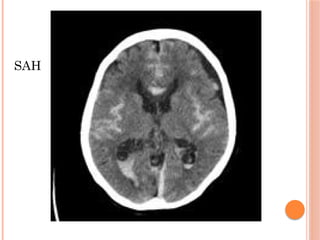

CT SCAN

 Haemorrhage appears instantly as a

hyperdense area

SAH